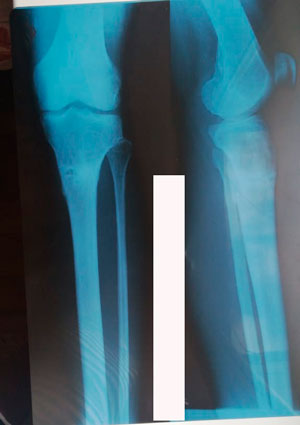

Дата операции - 07.11.2019г.

Дата снятия аппаратов - 15.02.2020

Срок сращения 92 дня.